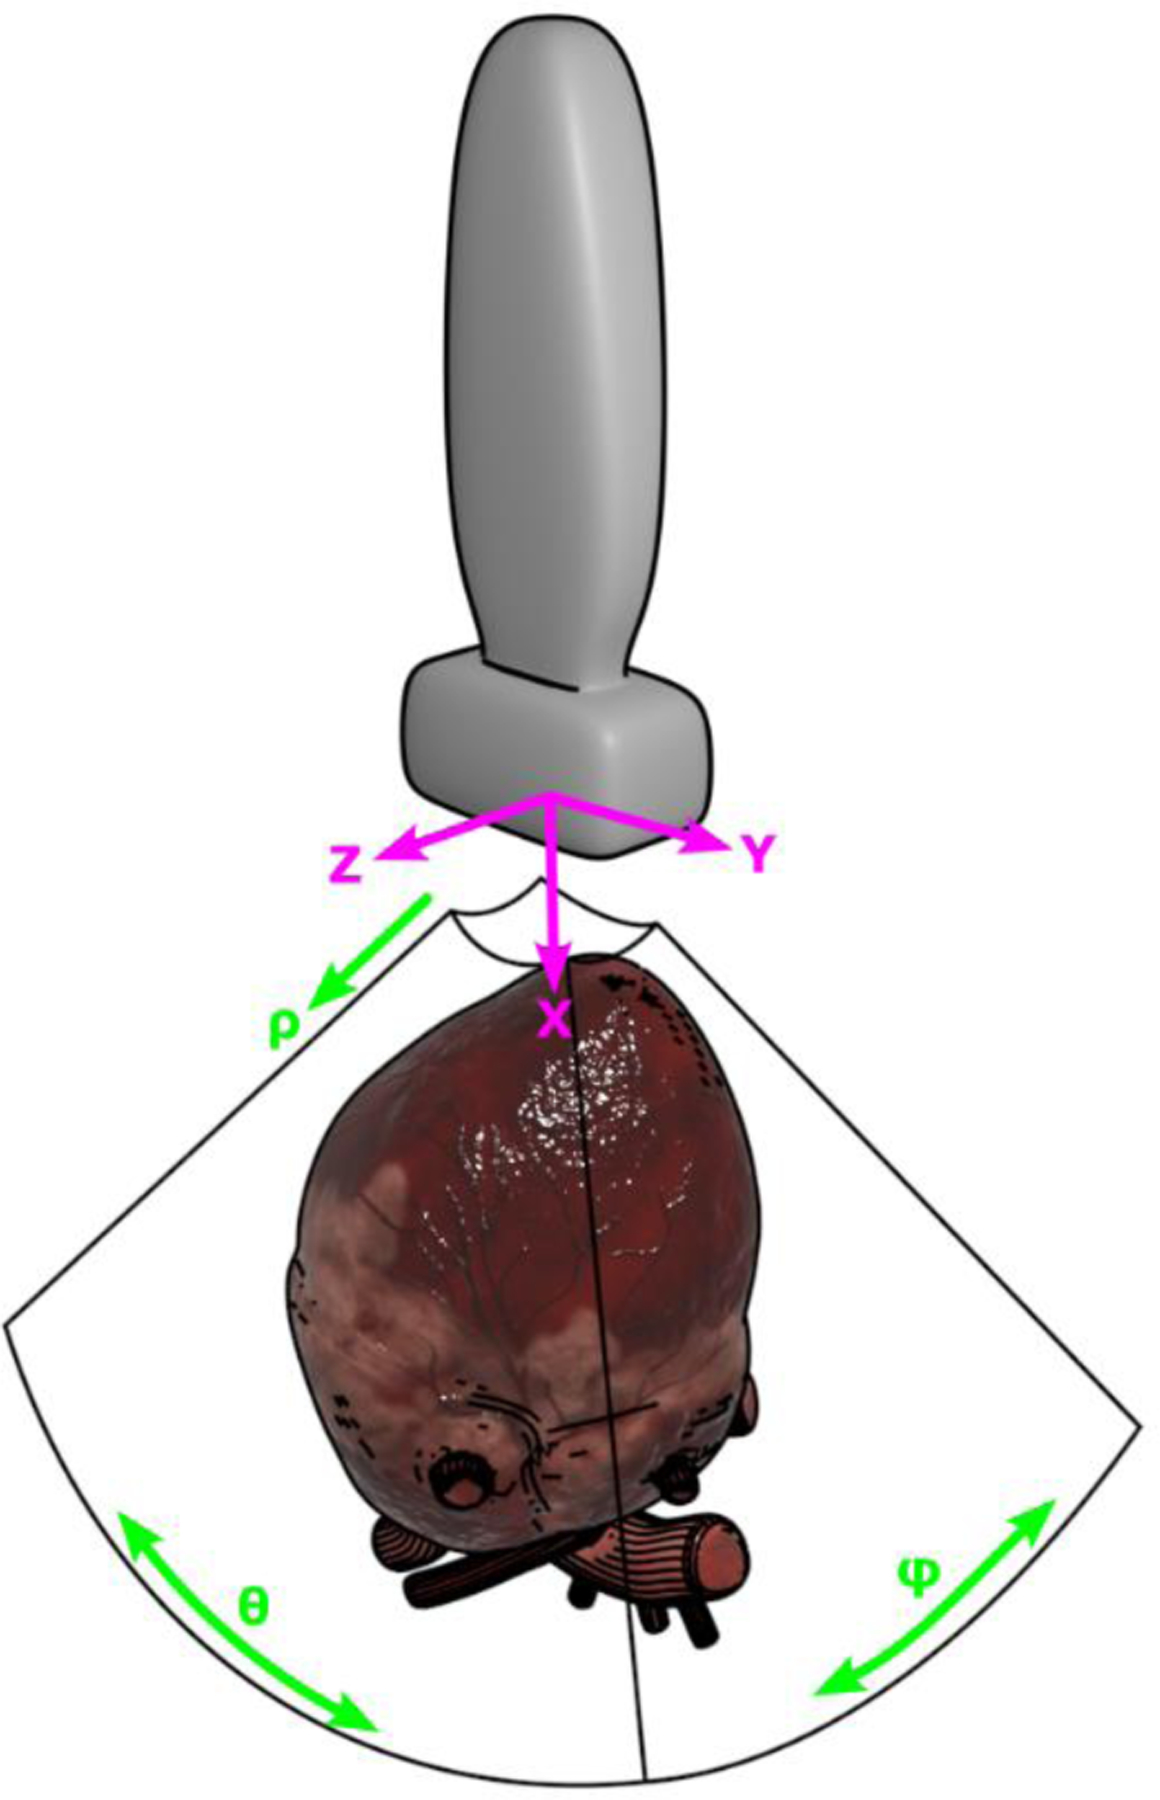

Advancements in medical imaging and artificial intelligence (AI) have revolutionized the field of cardiac diagnostics, providing accurate and efficient tools for assessing cardiac function. AI diagnostics claims to improve upon the human-to-human variation that is known to be significant. However, when put in practice, for cardiac ultrasound, AI models are being run on images acquired by human sonographers whose quality and consistency may vary. With more variation than other medical imaging modalities, variation in image acquisition may lead to out-of-distribution (OOD) data and unpredictable performance of the AI tools. Recent advances in ultrasound technology has allowed the acquisition of both 3D as well as 2D data, however 3D has more limited temporal and spatial resolution and is still not routinely acquired. Because the training datasets used when developing AI algorithms are mostly developed using 2D images, it is difficult to determine the impact of human variation on the performance of AI tools in the real world. The objective of this project is to leverage 3D echos to simulate realistic human variation of image acquisition and better understand the OOD performance of a previously validated AI model. In doing so, we develop tools for interpreting 3D echo data and quantifiably recreating common variation in image acquisition between sonographers. We also developed a technique for finding good standard 2D views in 3D echo volumes. We found the performance of the AI model we evaluated to be as expected when the view is good, but variations in acquisition position degraded AI model performance. Performance on far from ideal views was poor, but still better than random, suggesting that there is some information being used that permeates the whole volume, not just a quality view. Additionally, we found that variations in foreshortening didn't result in the same errors that a human would make.